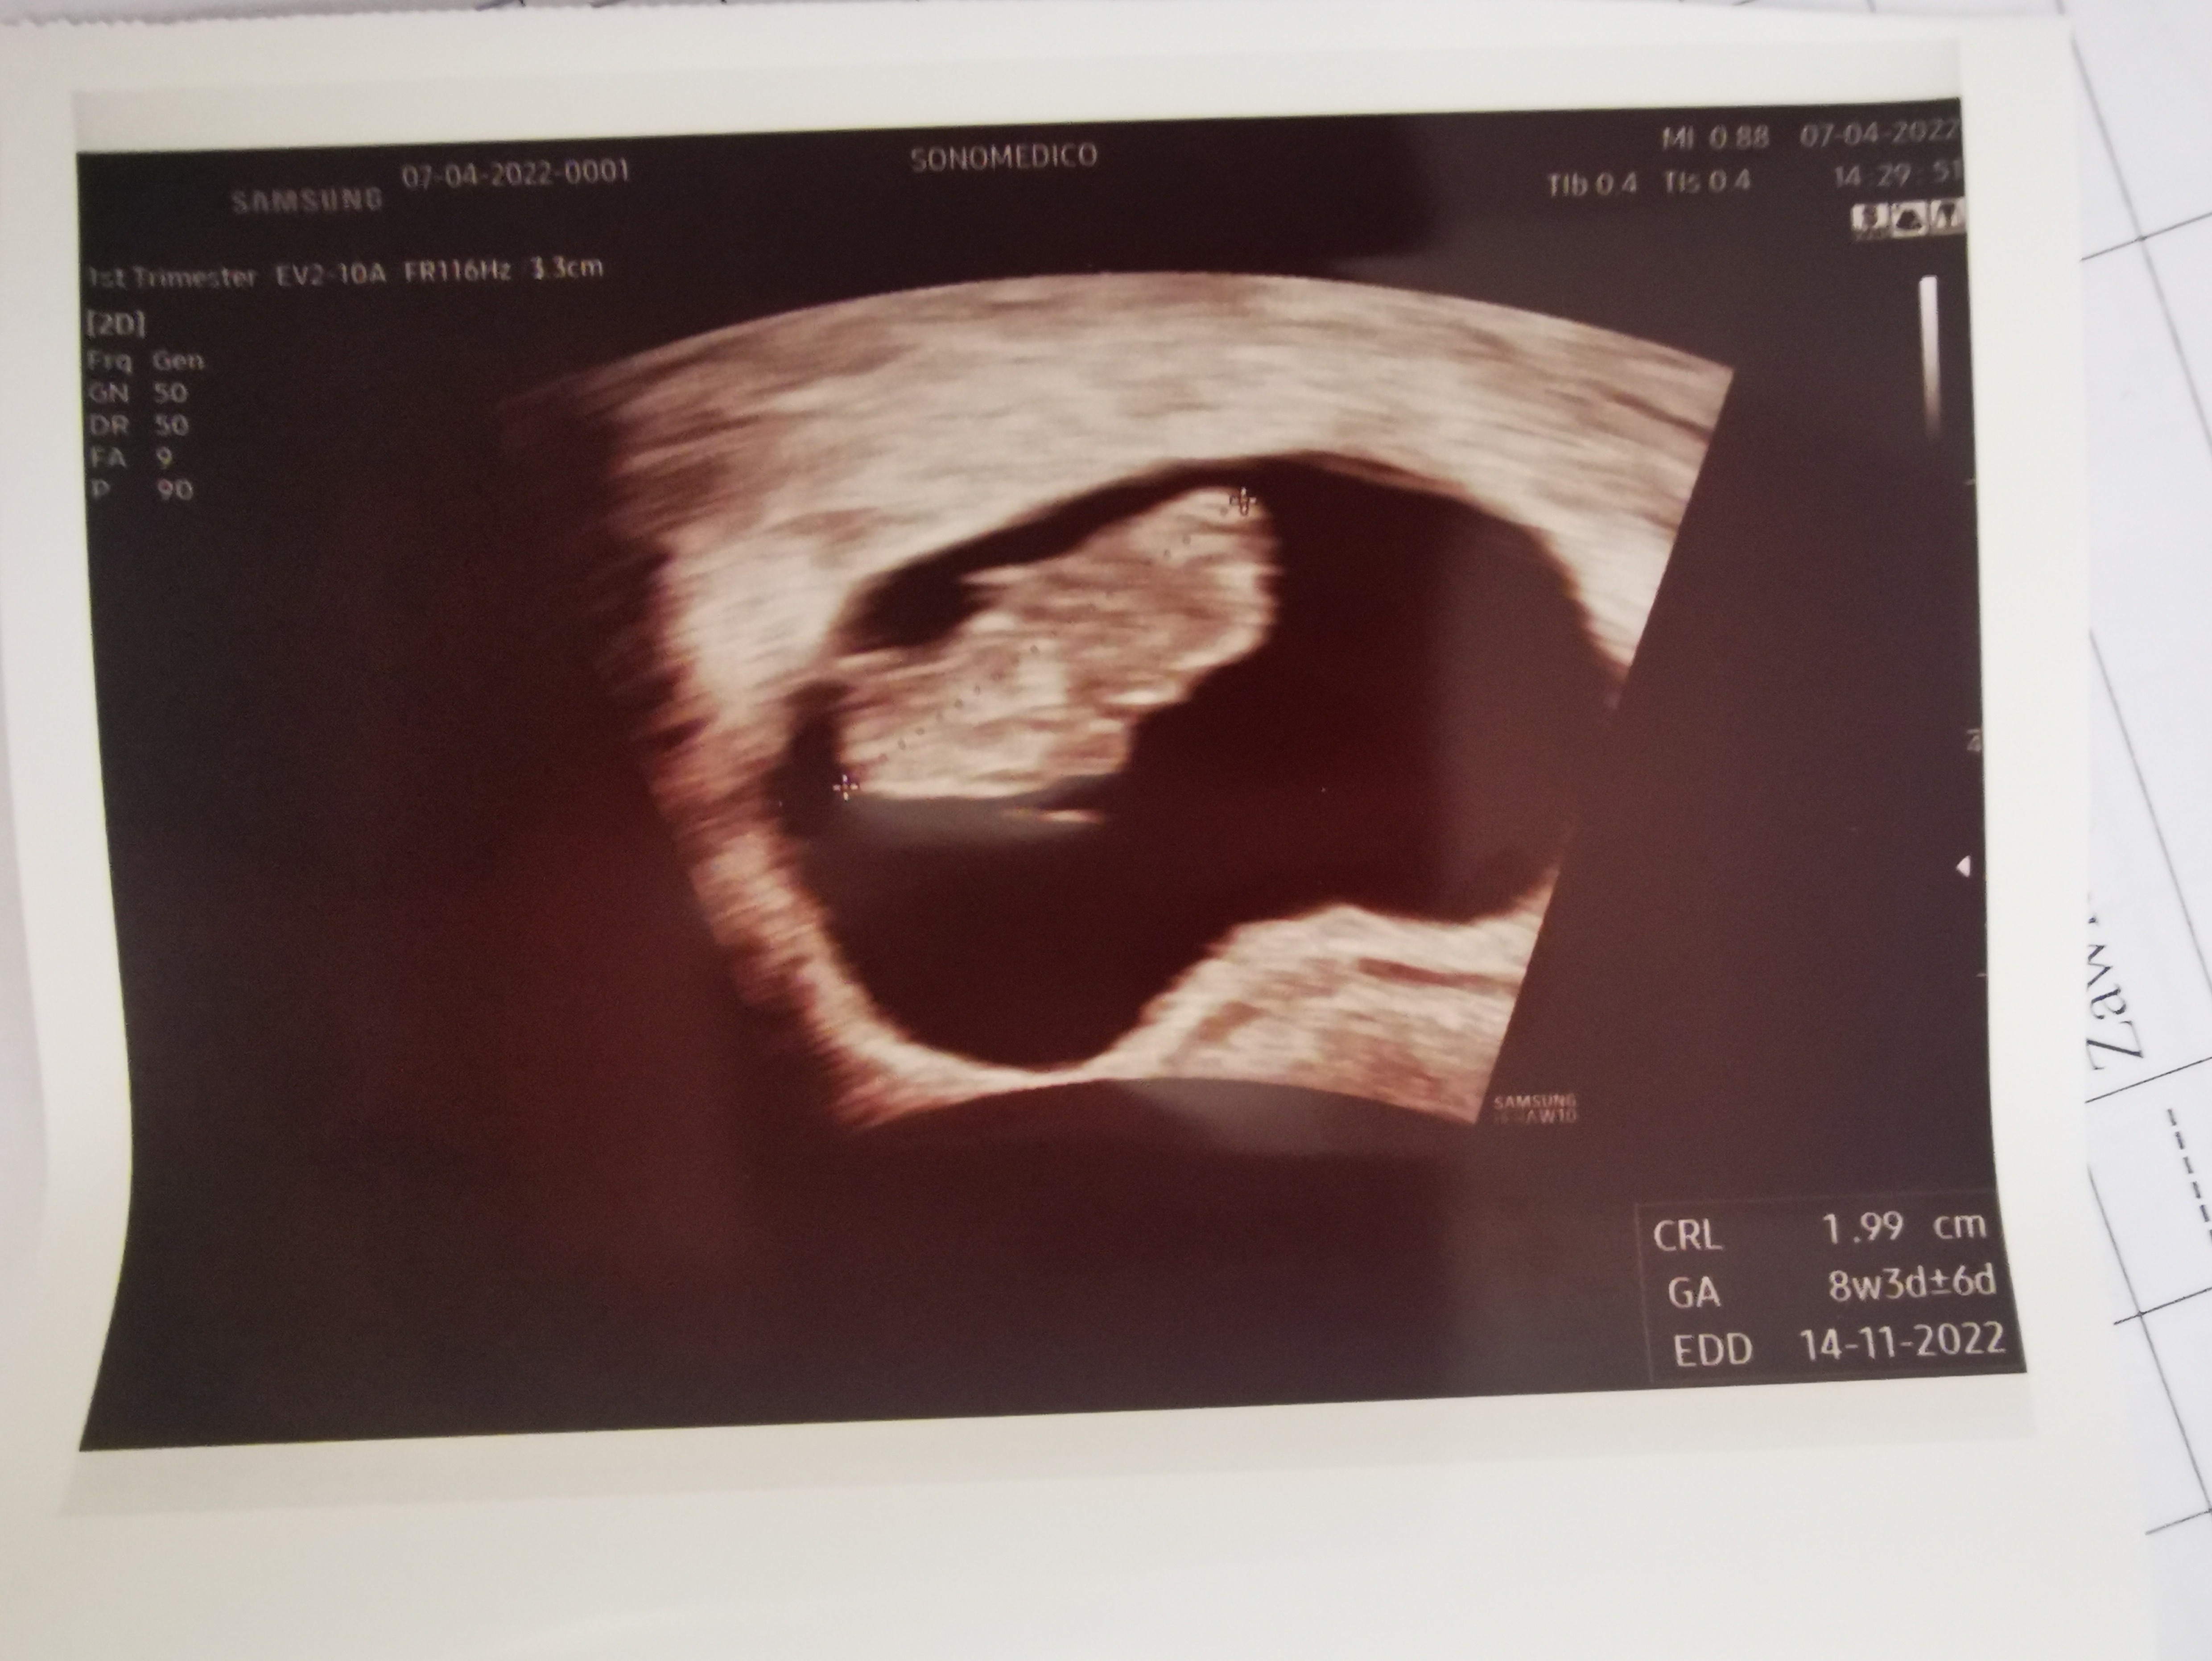

To jestem dzień do tyłu za tobą i mam bobasa o 1,7mm mniejszegoU mnie po wczorajszej wizycie 8+3 i termin na 14.11. Ciekawe, bo poprzednie usg miałam równo dwa tygodnie wcześniej i było 6+3 i też termin na 14.11. Więc chyba taki termin będzie faktycznie![]()

3cm to już kawał kawalera! Lub pannyJa po wizycie, babka straszna nawet zdjęcia nie dała tylko pozwoliła zrobić zdjęcie chociaż tobobo ruszało się żywo i ma całe 3 cm

termin teraz niby 5 listopada